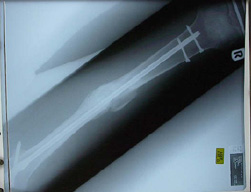

Smashed tib/fib

Here are the pics